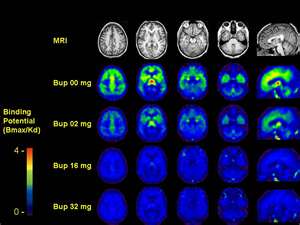

pet scan

pet-scan